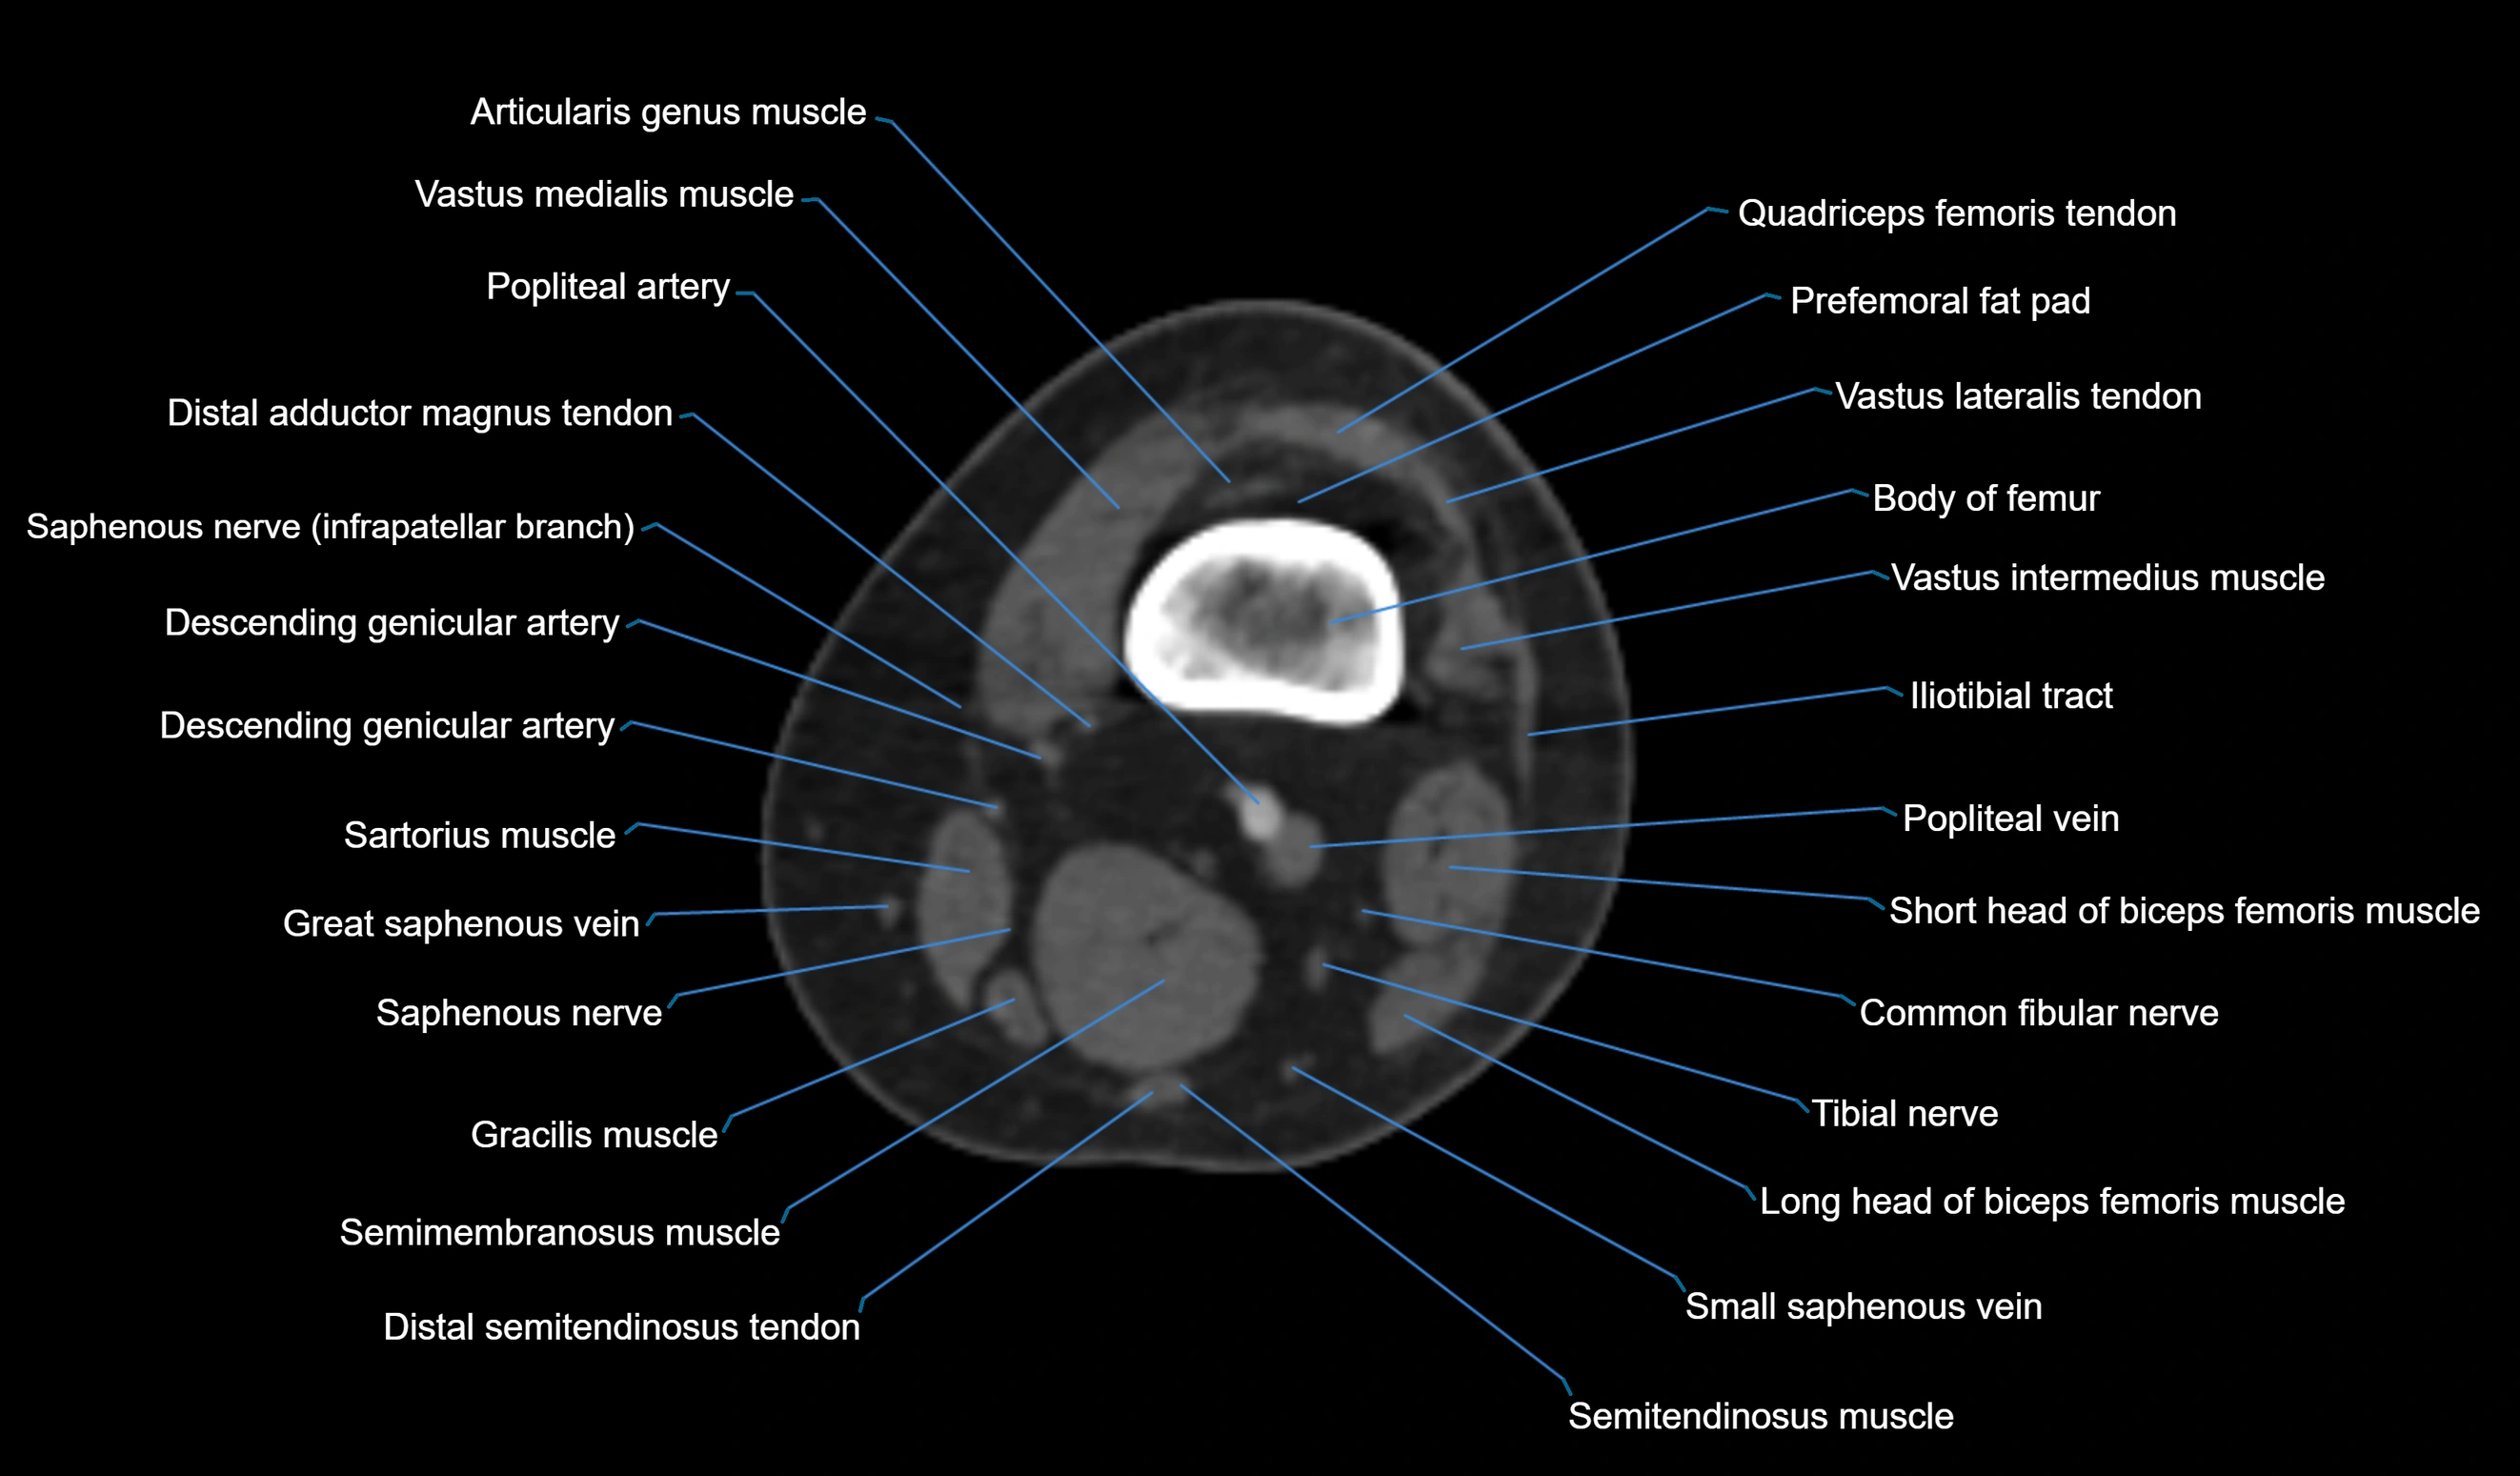

- Body of femur

- Common fibular nerve

- Distal adductor magnus tendon

- Distal quadriceps femoris tendon

- Distal semitendinosus tendon

- Distal vastus lateralis tendon

- Popliteal artery

- Popliteal vein

- Prefemoral fat pad

- Saphenous nerve

- Sartorius muscle

- Semimembranosus muscle

- Semitendinosus muscle

- Small saphenous vein

- Tibial nerve

- Vastus lateralis muscle

- Vastus medialis muscle

- great saphenous vein